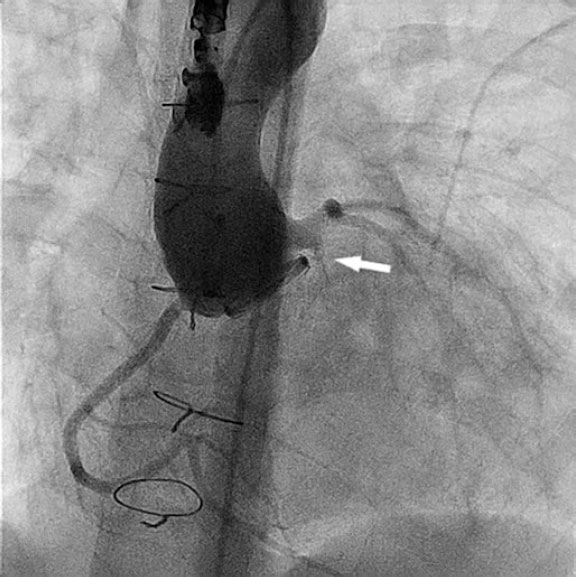

En la aortografía inicial no se detectó la fuga periprotésica, pero sí una dilatación del tronco coronario izquierdo de 6,5 mm y una fístula de este al ventrículo izquierdo de 2,4 mm de diámetro y 4,5 mm de longitud (figura 1 y vídeo S1).

Figura 1.